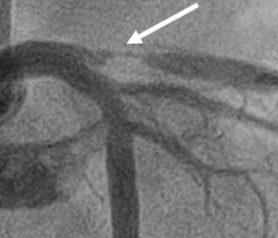

The term “LAD stenosis,” short for “left anterior descending artery stenosis,” describes a condition in which the left anterior descending coronary artery is obstructed or narrowed. This artery’s stenosis increases the risk of cardiovascular issues such as angina (chest discomfort), heart attacks, and other cardiovascular issues by reducing blood flow to the heart. Coronary artery disease, also known as coronary stenosis, is a common condition that happens when the arteries that carry blood to the heart become constricted or obstructed by plaque formation. LAD stenosis is one of the most frequent forms of coronary artery disease.

Significant obstructions of the LAD artery can be harmful because the LAD serves such a huge territory. The severity of a STEMI heart attack affecting the LAD is often higher than that of other types of heart attacks. Significant issues usually arise when the LAD artery is blocked by greater than 70%.